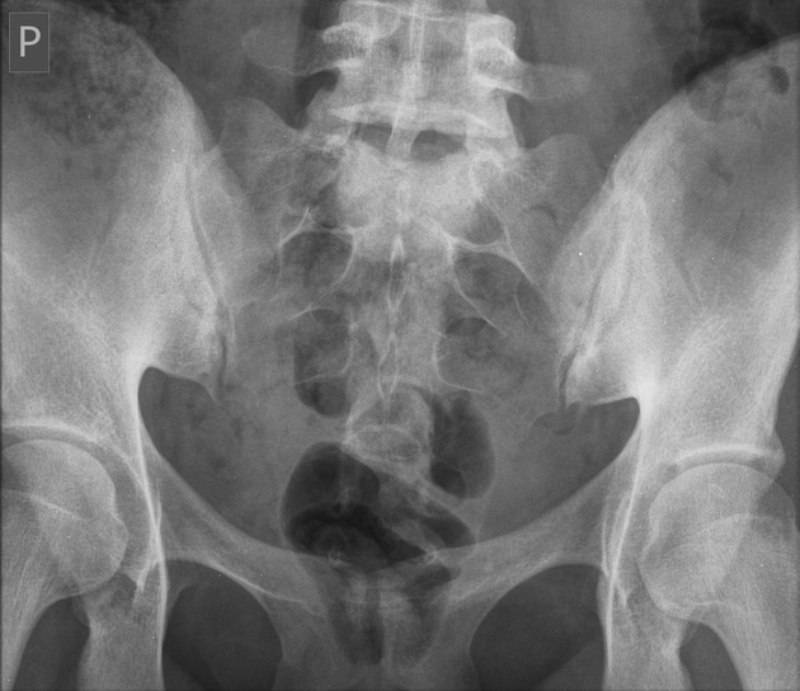

Viêm khớp cùng chậu thường khó chẩn đoán vì dễ bị nhầm lẫn với các tình trạng khác gây đau lưng dưới. Bác sĩ có thể chỉ định chụp X Quang, chụp cắt lớp (CT) hoặc chụp cộng hưởng từ (MRI) để chẩn đoán tình trạng này.

Tia X là một dạng bức xạ điện từ, giúp tạo ra hình ảnh về cấu trúc bên trong cơ thể. Loại tia này được phát hiện lần đầu vào năm 1895 và tia X chụp được hình ảnh mô người lần đầu tiên vào năm 1896 (2). Chụp X Quang là phương pháp chẩn đoán hình ảnh sử dụng phổ biến nhất. Bác sĩ có thể sử dụng X Quang để chẩn đoán các tình trạng liên quan đến xương chậu như:

Chụp X Quang vùng chậu là một phương pháp chẩn đoán đơn giản và không đau. Phụ nữ mang thai cần thông báo cho bác sĩ, vì thai nhi có thể bị phơi nhiễm với bức xạ từ tia X.